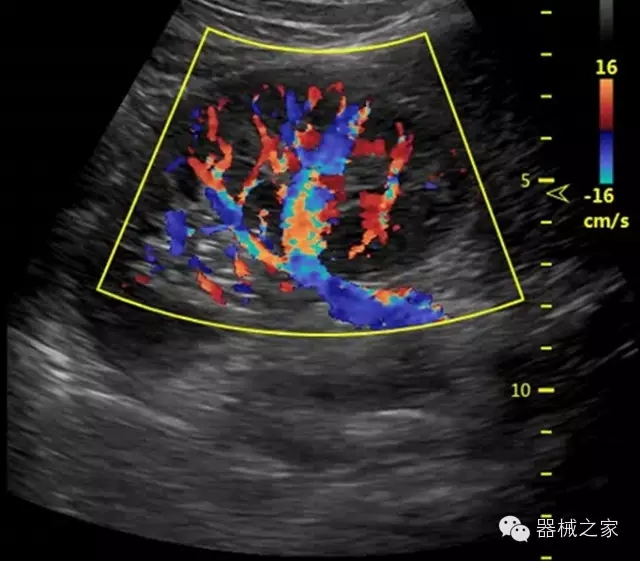

臨床圖片賞析

產(chǎn)品特點(diǎn)

優(yōu)異的成像技術(shù)

·亞陣元技術(shù):獨(dú)有的亞陣元技術(shù),對(duì)獨(dú)立晶片做二次切割,減少旁瓣偽像,增加臨床診斷的準(zhǔn)確性;

·μ-Scan微米成像技術(shù):開立獨(dú)有的μ-Scan技術(shù),還原出真實(shí)細(xì)膩、層次對(duì)比優(yōu)異的二維圖像;

·倒相諧波成像技術(shù):倒相諧波技術(shù)在去除基波信號(hào)的基礎(chǔ)上獲取兩倍二次諧波信號(hào),提高組織圖像的對(duì)比分辨力;

·智能微血流成像技術(shù):智能微血流捕捉技術(shù)可以提取出隱藏在背景噪聲中的弱血流信號(hào),大大提高低速血流的敏感性;